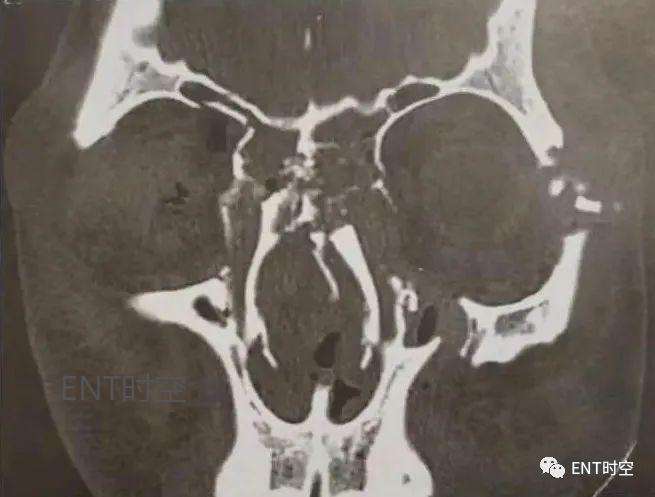

图6冠状位CT显示复合骨折,由于受面部前方外力,鼻面部凹陷压缩骨折,同时伴鼻中隔骨折。